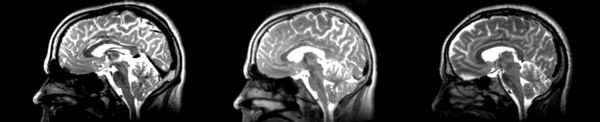

- 01053-t2 -> 01031-t2 = Result. All the images shown have the moving image on the left, the resultant image in the middle, and the target image on the right.

Rigid

01053>01031rigid.png = not bad... different brains of different sizes, but seem to be aligned in the ventricles so output seems okay. output slightly blurry. bad initial leveling displays.

Linear

01053>01031linear.png = not bad... different brains of different sizes, but seem to be aligned in the ventricles so output seems okay.output slightly blurry. bad initial leveling displays.

Affine

01053>01031_affine.png = looks good in terms of size. odd warping of frontal lobe and cerebellum area, but otherwise good coregistration.

B-spline

01053>01031_bspline.png = looks good in terms of size. odd warping of frontal/temporal lobe and cerebellum area, but otherwise good coregistration.

Diffeomorphic Demons

01053>01031_demons.png = 10 minutes. Window/leveling initially off. Otherwise, it looks really good. Not much distortion.